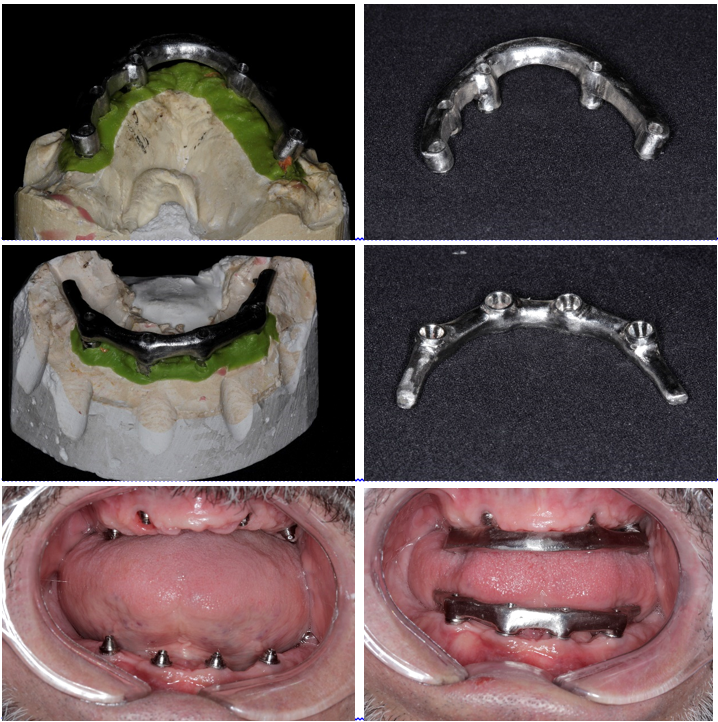

Abaixo a descrição das etapas de confecção das próteses protocolos superior e inferior:

1- seleção dos pilares intermediários (mini-cônicos), instalação e moldagem de transferência. Obtenção dos modelos de trabalho e confecção de base de prova e planos de cera com o uso de dois componentes (cilindros de metal para provisório do pilares mini-cônicos);

2- orientação dos planos de cera sobre as bases de prova (orientar suporte de lábio, altura incisal em repouso e no sorriso forçado, orientar plano de Camper e linha bipupilar, corredor bucal, dimensão vertical de repouso, de oclusão) para registro maxilo-mandibular. Seleção dos dentes e montagem dos dentes em laboratório;

3- prova da montagem dos dentes em cera – prova funcional. Aferição da estética e da função mastigatória. Envio ao laboratório para confecção do enceramento, fundição e acabamento/polimento da barra metálica;

4- prova e ajustes da barra metálica na boca do paciente;

5- prova dos dentes montados sobre a barra metálica;

6- instalação e ajustes das próteses.